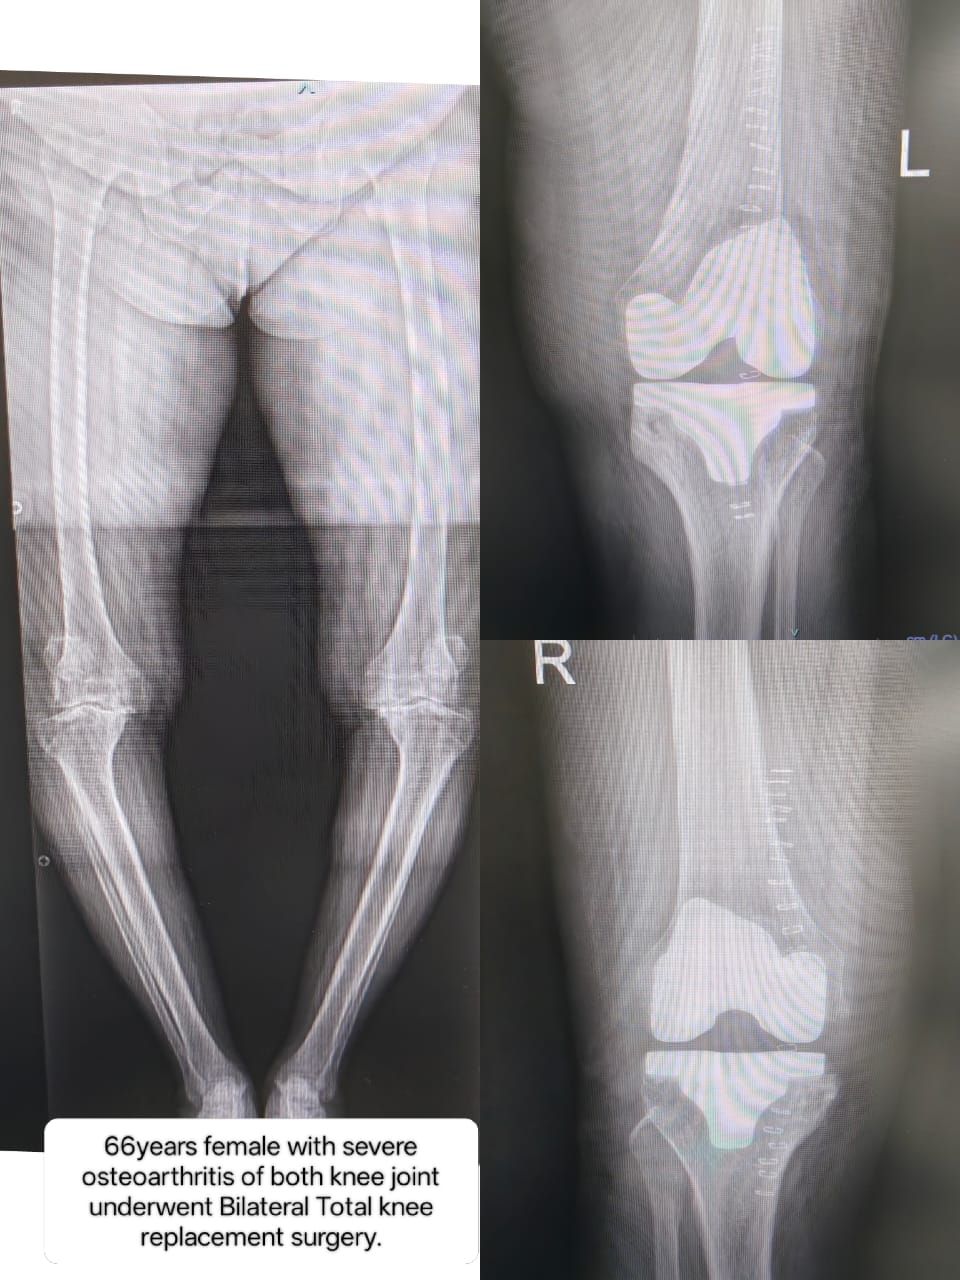

Successful Bilateral Total Knee Replacement Surgery: Restoring Mobility in Severe Osteoarthritis at Vyom Ortho Care